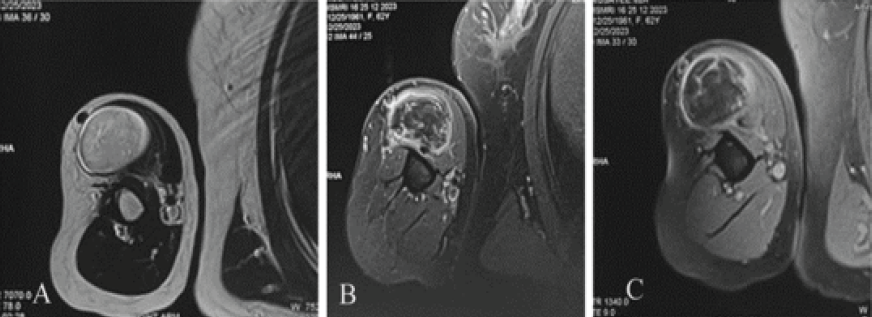

The lesion showed iso-intensity with fat in T1-weighted images and suppression with heterogeneous signals on T2-weighted images (Fig. 2).

Figure 2: Axial sections of magnetic resonance imaging of the right shoulder. T2-weighted axial sequence showing a well-defined space occupying lesion isointense with subcutaneous fat and thin hypointense streaks suggestive of lipomatous lesion and minimal fibrous septae. (a) T1 fat suppression post-contrast axial sequence showing hypointense lesion in long head of biceps tendon with heterogeneous enhancement and fibrous septa enhancement along with a smooth peripheral capsule enhancement (b and c). Fine-needle aspiration cytology of the swelling showed fat globules with inflammatory cells; hence, an excision biopsy was planned. Under general anesthesia and interscalene block with patient in beach chair position, a deltopectoral approach was performed and the mass was found within the long head of biceps tendon without any infiltration to adjacent structures. Diagnostic shoulder arthroscopy was performed and the rupture was found at the proximal attachment of the long head of biceps tendon and tenotomy was completed. The biceps tendon was excised distally at the level of conjoint tendon. The excised mass with tendon was of size 6.5 × 4.5 centimeters and firm in consistency. The cut surface appeared yellow tan with densely packed contents with septations. Histopathological examination showed mature adipocytes with mixed inflammatory cells in the septa exhibiting a granulomatous septal panniculitis like picture and negative for murine double minute 2 (MDM2) expression (Fig. 3).